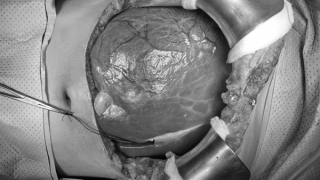

Kết hợp với kết quả siêu âm cho thấy, bệnh nhân bị đa u xơ tử cung, kích thước lớn 20cmx10cm, nên các bác sĩ chỉ định phải phẫu thuật ngay. Trước khi phẫu thuật, do thiếu máu nên bệnh nhân được truyền gần 4 đơn vị máu.

BS.CKII Trương Quốc Việt, người trực tiếp thực hiện ca phẫu thuật cho biết, khối u khá lớn, chèn ép các tạng xung quanh, khiến niệu quản bị lệch nên ca phẫu thuật gặp nhiều khó khăn. Ê kíp phẫu thuật đã phải rất cẩn thận, tỉ mỉ, khéo léo để bóc tách khối u cho bệnh nhân.

Sau gần 2 tiếng rưỡi đồng hồ, các bác sĩ đã thực hiện thành công ca phẫu thuật, lấy toàn bộ khối u nặng 2kg ra khỏi tử cung cho bệnh nhân.